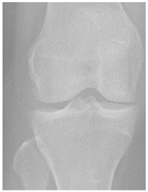

3.1. Dataset Description